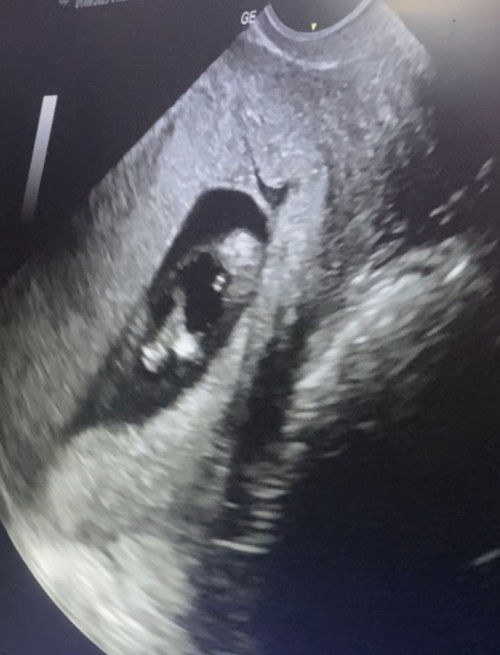

Hello po ! 🫶🏻 Im 11 weeks and 5 days na po ang kaka pa trans V ko palang, sinilip namin yung gender

Sa tingin nyo po ano kaya gender nya? Hehehe excited lang po. See photo below 🫶🏻

mima wala papo tlg gender Yan nag pa trans v din Ako at 12 weeks wala pa possible daw na sa 14weeks Makita na